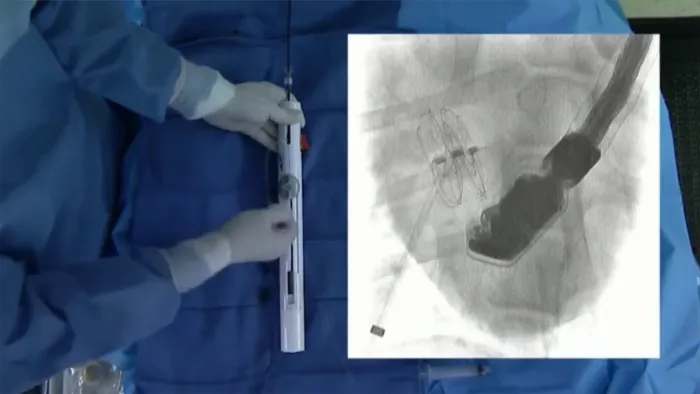

ゴア® カーディオフォーム セプタルオクルーダーの留置アニメーション

本資料に記載の図版はイメージです。

展開手順